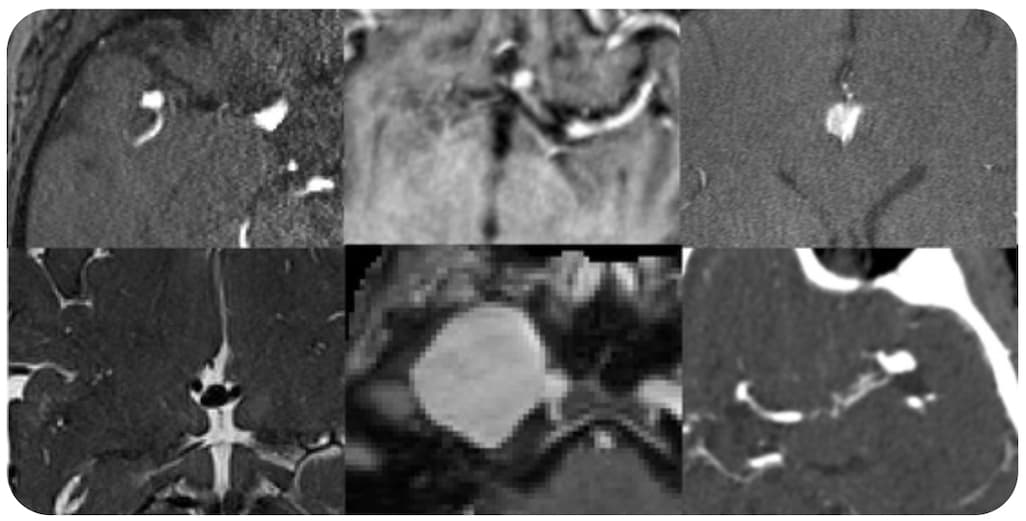

L'objectif du concours d’IA pour la détection des anévrismes intracrâniens de la RSNA était de développer des modèles deep learning capables de détecter et de localiser les anévrismes intracrâniens sur diverses modalités d'imagerie médicale.

Lancé en juillet 2025 sur la plateforme Kaggle, le concours a attiré 1 147 équipes du monde entier. La phase de compétition s'est terminée en octobre et les solutions primées ont ensuite été examinées par une équipe d'experts bénévoles en IA afin de confirmer les résultats. Les neuf équipes citées plus haut se sont partagé un prix total de 50 000 $ et ont été mis à l'honneur au Théâtre de l'IA (lors du congrès RSNA 2025.